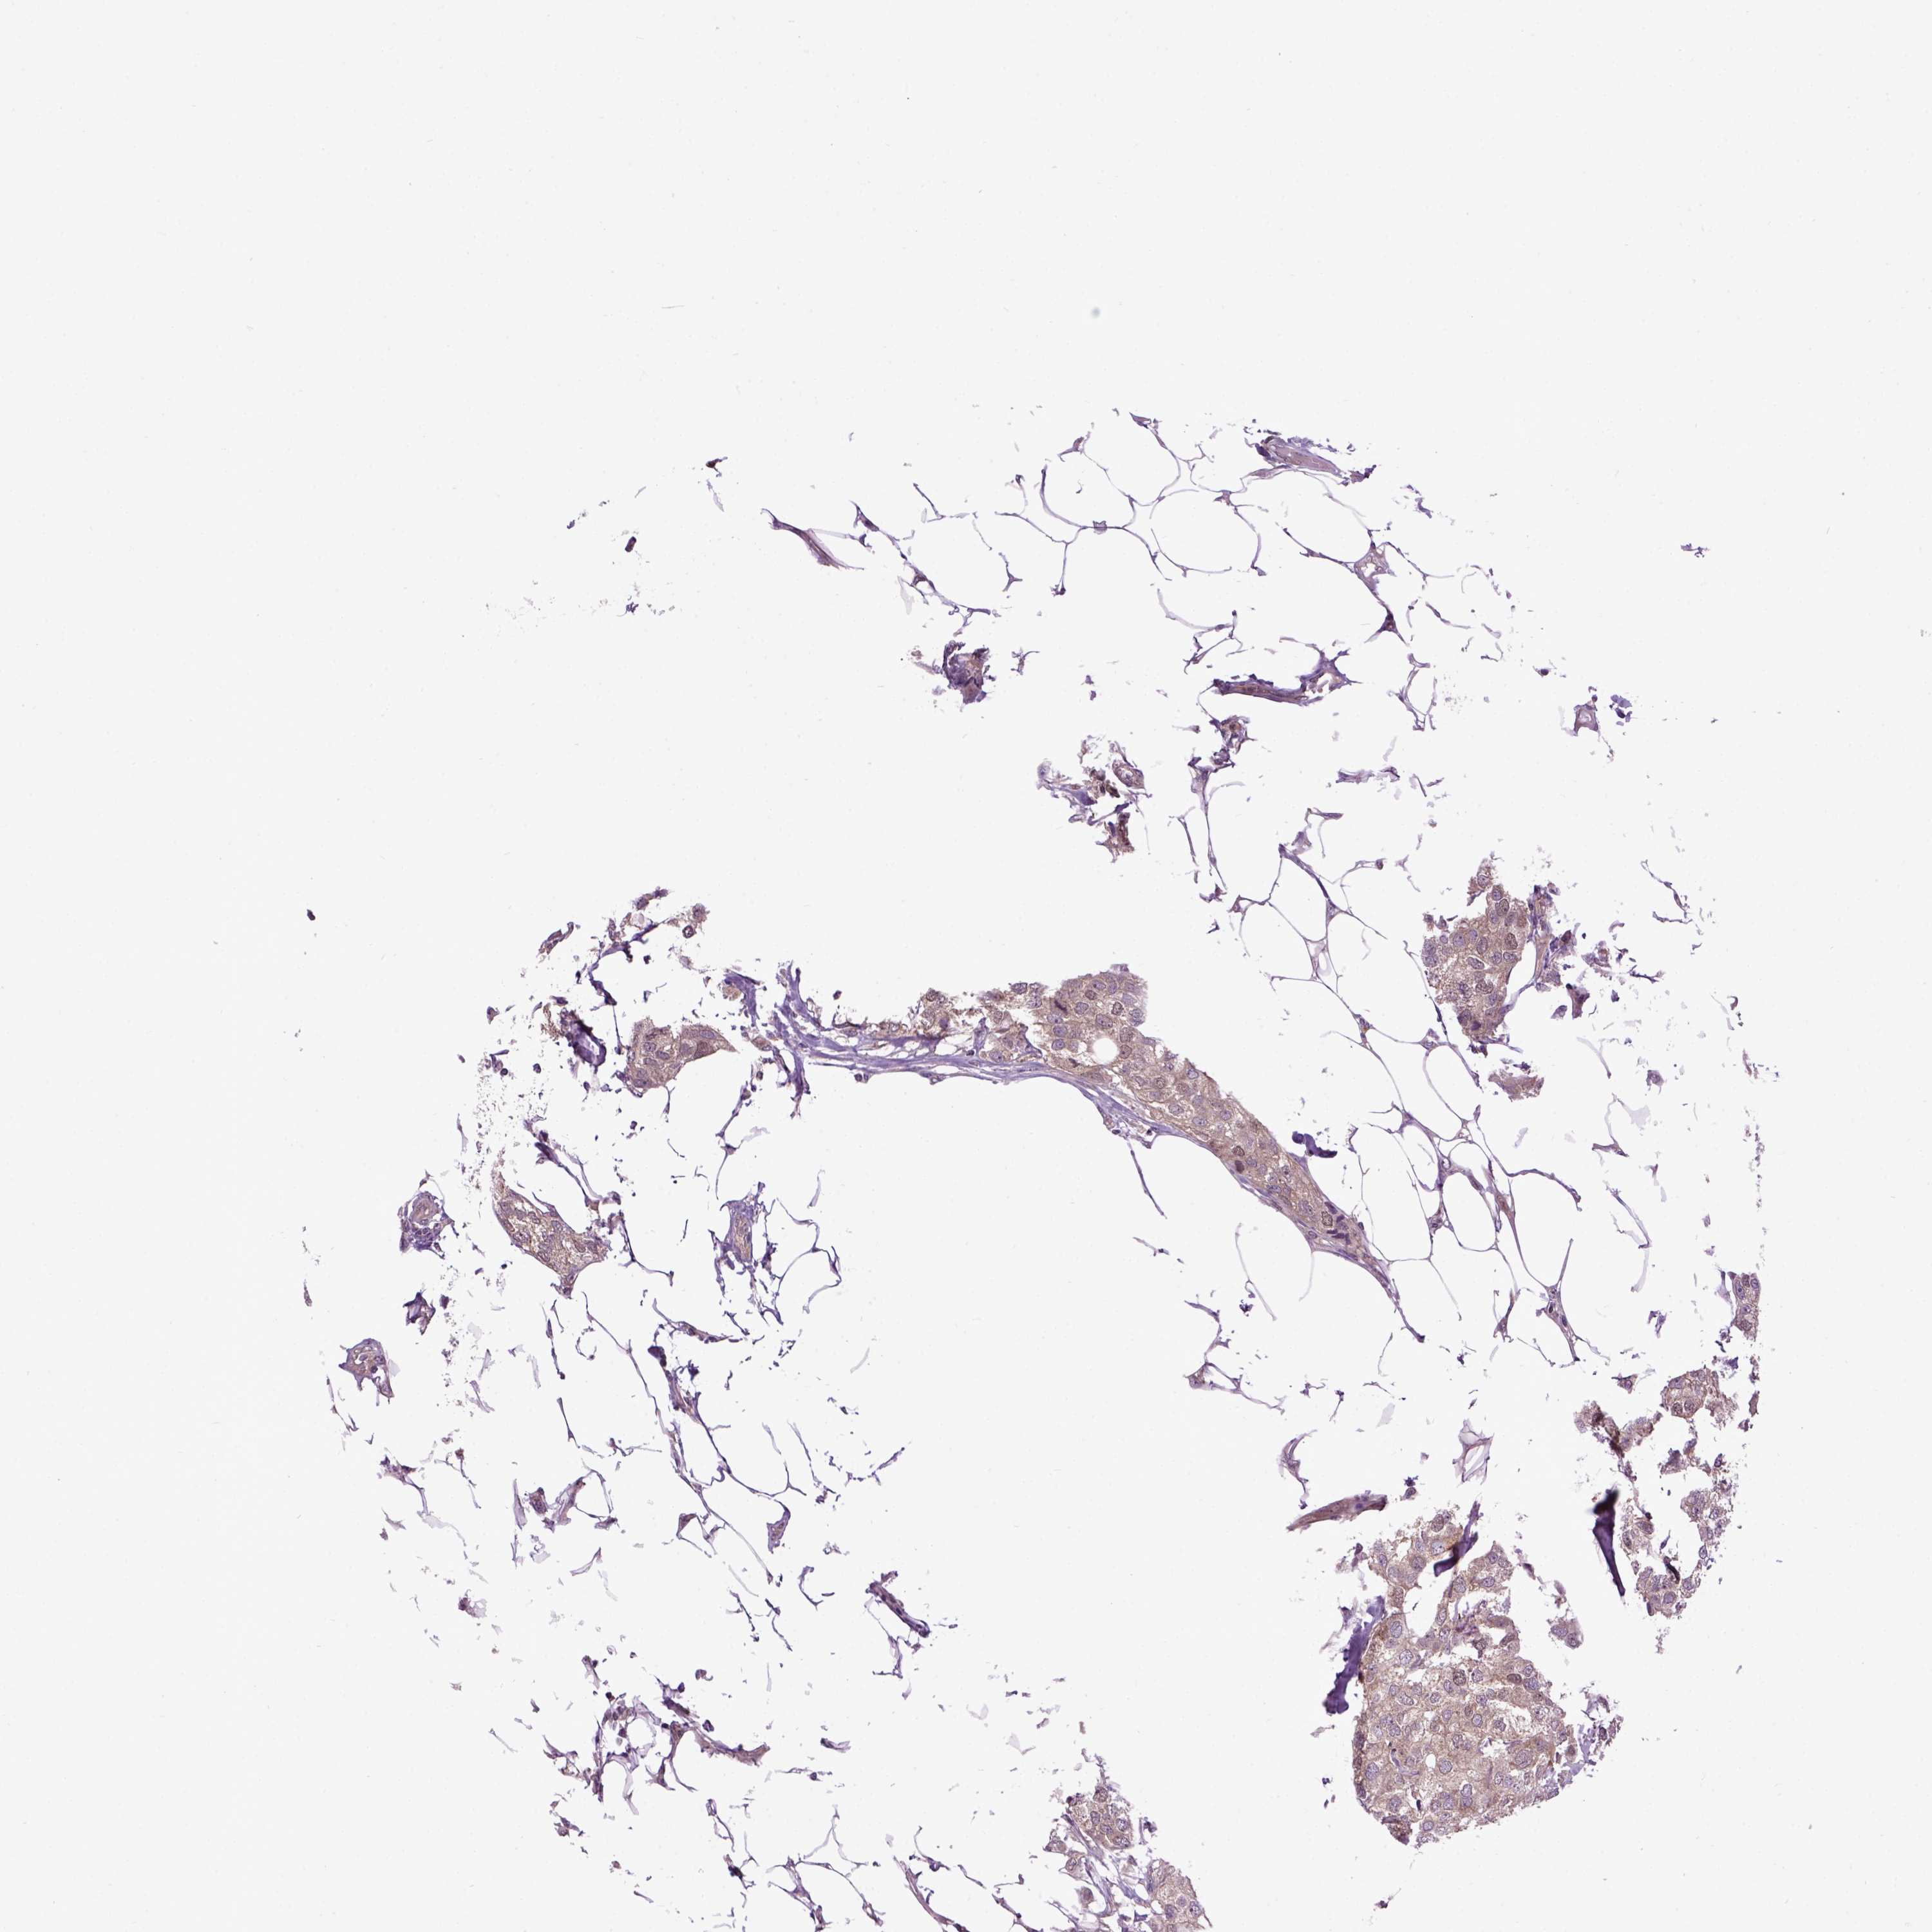

CANCER BREAST CANCER Show tissue menu

BRCA TCGA BRCA VALIDATION PROTEIN EXPRESSION